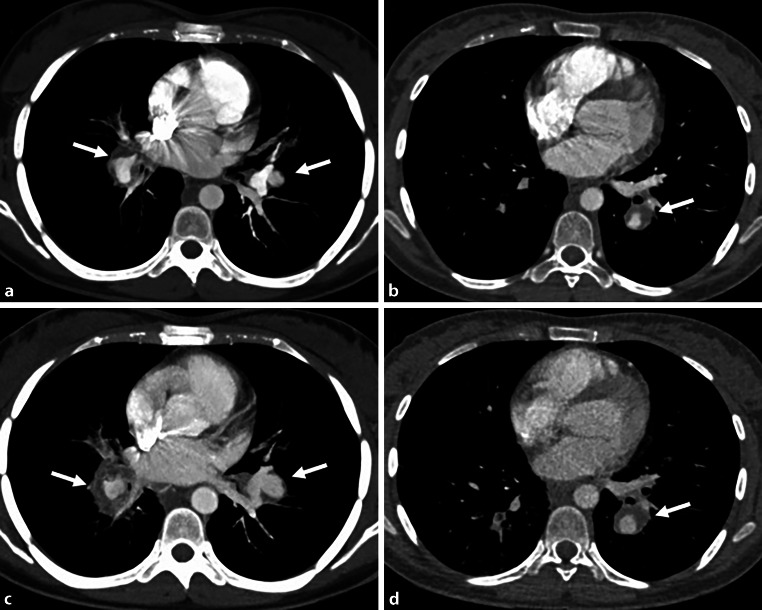

After one more severe episode of hemoptysis 3 weeks after initial presentation, the patient underwent another CT examination, which revealed progression of the diameter of the aneurysms of the main pulmonary arteries (Fig. 2a–d) and multiple patchy ground-glass opacites, compatible with a pulmonary hemorrhage. Abdominal CT showed a complete obliteration of the inferior vena cava due to thrombus and fibrotic changes over the entire length. The liver showed parenchymal perfusion abnormalities and thrombosis of the left and middle hepatic vein consistent with Budd-Chiari syndrome (Fig. 3).

Fig. 2.

CT pulmonary angiography at presentation (a and b) and CT follow-up after 3 weeks (c and d) showing a progression of the pulmonary artery aneurysms on both sides (arrows) (on the right side, from 2 to 2.6 cm, on the left side, from 1.4 to 1.9 cm)